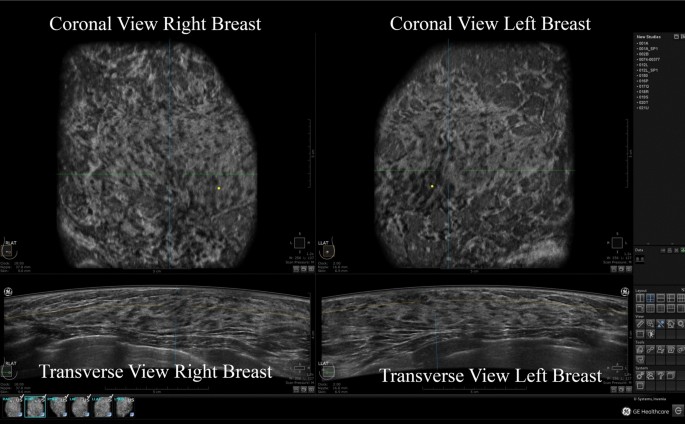

The Value Of Coronal View As A Stand Alone Assessment In Women Undergoing Automated Breast Ultrasound Springerlink

Figure 2 From Automated Whole Breast Ultrasound Semantic Scholar

Automatic Breast Ultrasound State Of The Art And Future Perspectives Ecancer